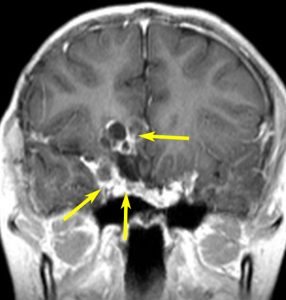

7歳の子が視力障害で発症しました。両耳側半盲という症状です。典型的な鞍隔膜下頭蓋咽頭腫です。ガドリニウム造影剤を入れないMRIでみえる,黄色い矢印の先の白い高信号は抗利尿ホルモンです。ですから下垂体機能もまだ残っていて,尿崩症はありません。視力障害が戻らないことがあるのでなるべく早く,経鼻的な手術で摘出した方がいいものです,簡単 o(^-^)o